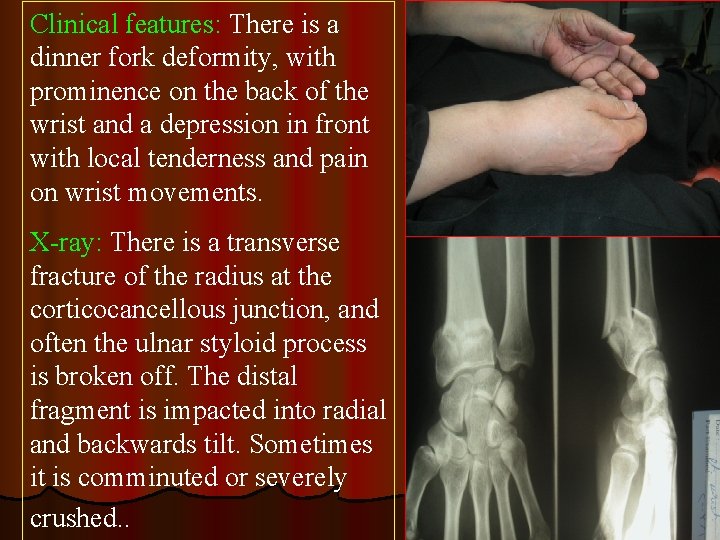

Clinical features: There is a dinner fork deformity, with prominence on the back of the wrist and a depression in front with local tenderness and pain on wrist movements. X-ray: There is a transverse fracture of the radius at the corticocancellous junction, and often the ulnar styloid process is broken off. The distal fragment is impacted into radial and backwards tilt. Sometimes it is comminuted or severely crushed. .